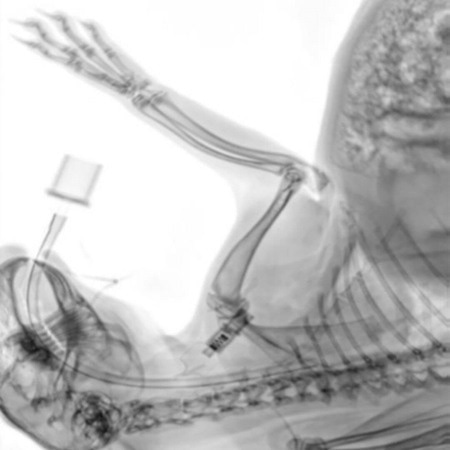

Intraoperative control image of a rabbit. The position of the intubation can be determined with great precision.

Intraoperative control image of a rabbit. The position of the intubation can be determined with great precision. Image Credit: Scintica Instrumentation Inc